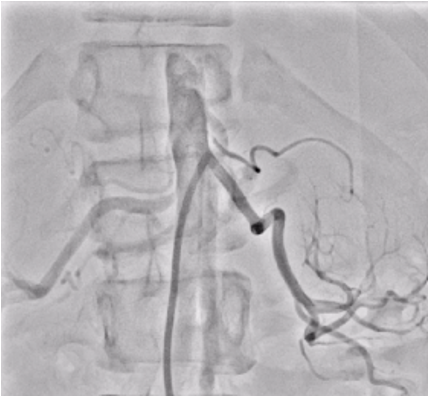

Six french femoral arterial sheath was placed under ultrasound guided. Renal angiogram using 6 Fr Renal Double Curve catheter showed normal left renal artery and subtotal occlusion near at the ostium of right renal artery.

Despite having an overlay from three dimensional three dimensional fusion imaging, it was difficult to wire the right renal artery. Five French right brachial arterial sheath was introduced under ultrasound guided. Polymer jacket coronary guide wire was used under two dimensional three dimensional fusion imaging. Wiring was finally succeeded with the support of JR 3.5/ 5 Fr guiding catheter from the brachial access. Lesion was predilated using 2.0 x 15 mm and 4.0 x 15 mm semi compliant coronary balloons. Drug eluting stent of 4.0 x 15 mm was implanted and post dilated using 4.5 x 12 mm non compliant coronary balloon. The procedure was uneventful. Fluoroscopy time was 53.16 minutes, contrast volume was 130 cc, radiation dose was 83.88 mGy.